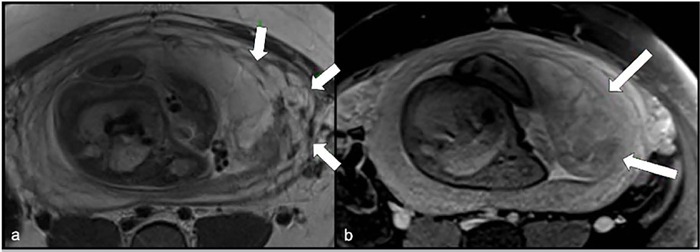

妊娠滋养细胞疾病(GTD)包括由双胎妊娠受精期间发生的遗传异常引起的异质性疾病,通常可能与辅助生殖技术有关。一种极其罕见的GTD的表现是双妊娠葡萄胎与胎儿共存,这种情况可能是母亲和胎儿并发症的重要原因。一名36岁的女性(G2, P0, A1)接受了友好的卵巢控制刺激(COS),然后进行了宫内人工授精(IUI)以辅助生殖为目的,导致双胎妊娠,最初的特征是两个妊娠囊。然而,一个囊未能发育,而是退化为磨牙滋养细胞疾病,而另一个则维持正常胎儿的正常生长。在妊娠33周时,患者出现先兆子痫,需要在三级医疗机构进行剖宫产。生殖辅助手术可能与滋养细胞疾病有关。此外,囊性病变的存在需要广泛的鉴别诊断,磁共振成像是准确评估和区分结构的有价值的工具。

Gestational trophoblastic diseases (GTD) comprise a heterogeneous group of disorders arising from genetic anomalies occurring during fertilization in twin pregnancies and often may be associated with assisted reproductive techniques. An exceedingly rare presentation of GTD is a twin pregnancy hydatidiform mole with a co-existing fetus, condition which may be an important cause of complications for the mother and the fetus. A 36-year-old woman (G2, P0, A1) underwent a friendly controlled ovarian stimulation (COS) followed by intrauterine insemination (IUI) for assisted reproductive purposes, resulting in a twin pregnancy initially characterized by two gestational sacs. However, one sac failed to progress and instead degenerated into molar trophoblastic disease, while the other sustained a normal fetus with regular growth. At 33 weeks gestation, the patient developed preeclampsia, necessitating delivery via cesarean section at a tertiary care facility. Reproductive-assisted procedures may be linked to cases of trophoblastic disease. Additionally, the presence of cystic lesions warrants a wide differential diagnosis, with magnetic resonance imaging serving as a valuable tool for accurate assessment and differentiation of structures.